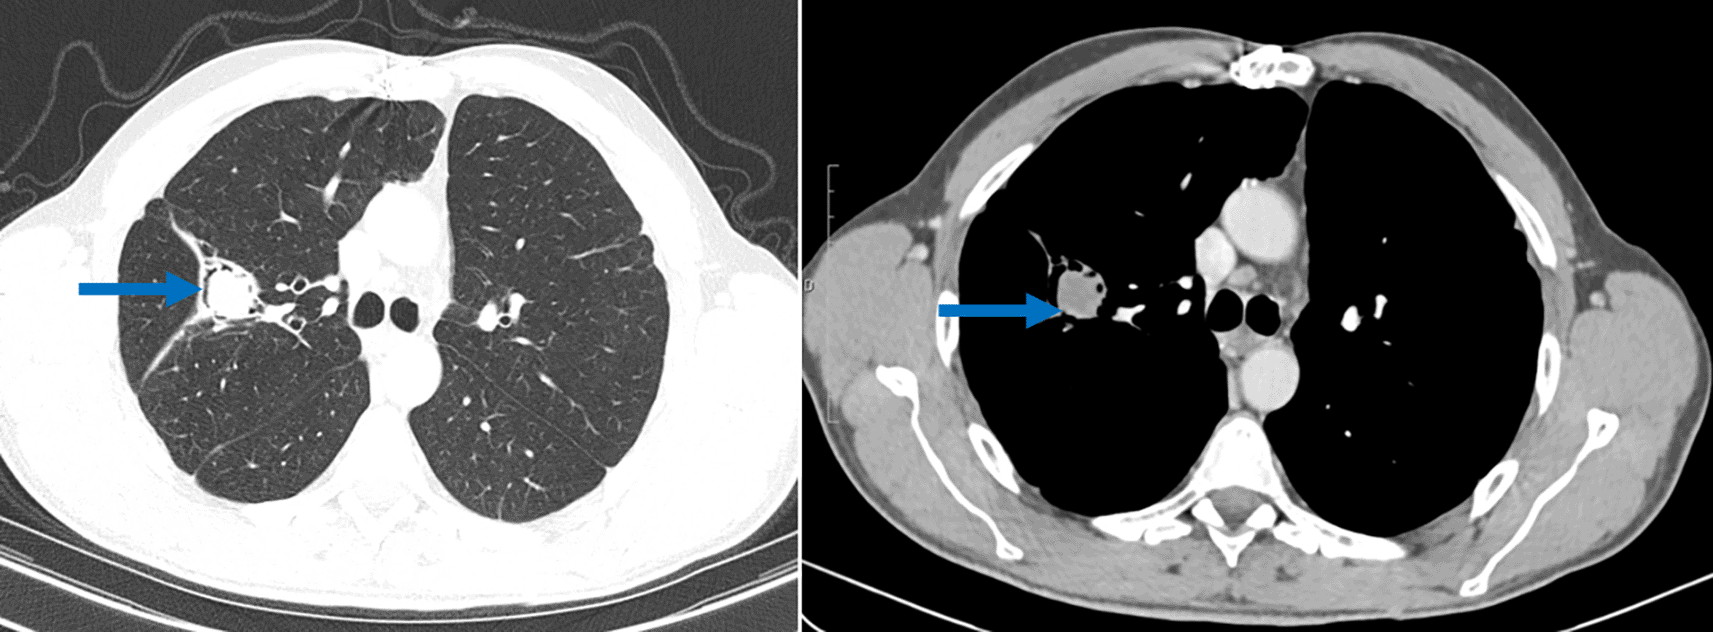

During a regular post-surgical follow up, a scannographic image of a fluid-density endo-bronchial material in the right superior lobe (lung cavity sequelary to the previous cystectomy) of the lung separated from the cavity wall by an airspace (“air crescent” sign) was found, this image is typical of pulmonary aspergilloma (Figure 3). Even though the Aspergillus serology showed doubtful results, the clinical context coupled to the CT scan findings were highly suggestive of a pulmonary aspergilloma. Blood work up showed high levels of IgE. A surgical resection of the cavity is programmed but not yet performed.

Another intriguing finding in this case report is the discovery of an aspergilloma, on a lung cavity. Pulmonary aspergilloma occurs as a colonizer of pre-existing pulmonary cavity of any etiology such as sequelae tuberculosis, cavitary neoplasia or operated hydatid cyst and it is a saprophytic infection.9 Aspergilloma has rarely been described in operated hydatid cyst cavities in immunocompetent patients.10 For this patient, the aspergilloma was discovered two years after the lung surgery. A very similar case of a 56-year-old patient, who presented with an aspergilloma of the upper right lobe following cystectomy, have been described by M. El Hammoumi et al.10